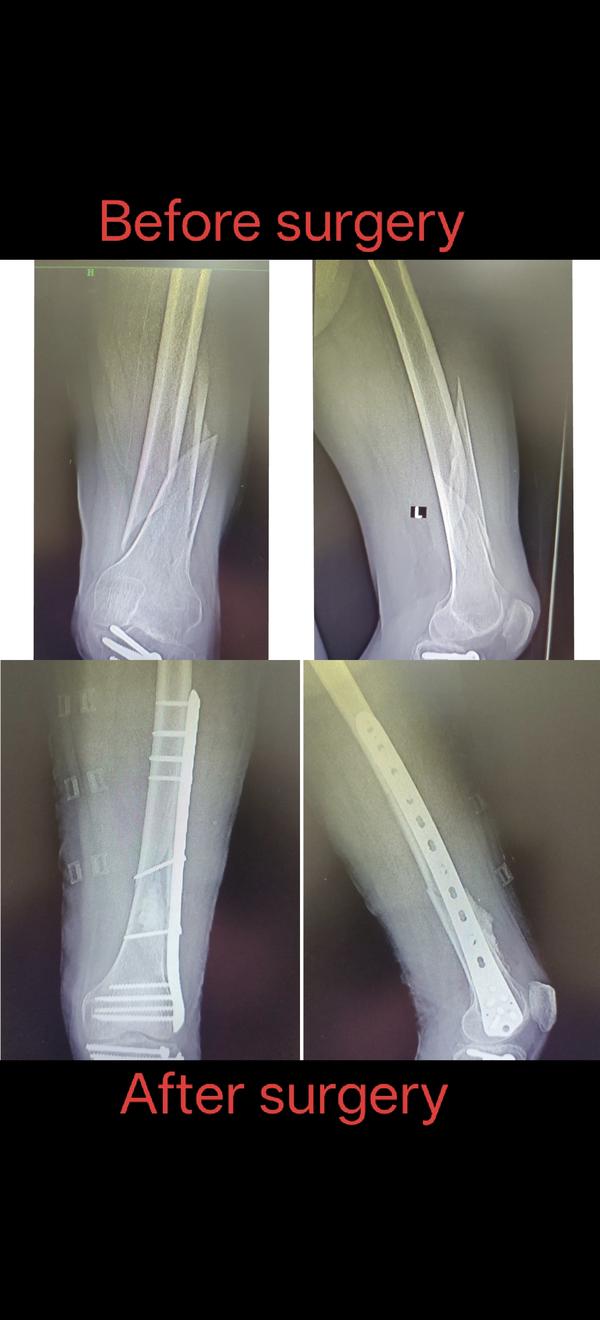

Welcome to the world of orthopedic excellence, where your health and well-being are our utmost priorities. Dr. Chetan Singh , an accomplished orthopedic surgeon, has been a dedicated practitioner in the vibrant city of Bhopal for the past 8 years. His unwavering commitment to providing exceptional orthopedic care has earned him a reputation as a trusted healthcare professional in the region. Meet Dr. Chetan Singh is a highly skilled orthopedic surgeon who has dedicated his career to improving the lives of patients suffering from orthopedic conditions. His educational journey began with the completion of an MBBS degree from Devi Ahilya Vishwa Vidyalaya, Indore, M.P. in 2015, where he laid the strong foundation for his medical expertise. Driven by his passion for orthopedics and a desire to offer the best care possible, Dr.Chetan Singh continued his educational journey. In 2019, he successfully achieved a Master of Surgery (MS) in Orthopedics from Madhya Pradesh Medical Science University, Jabalpur. This rigorous training equipped him with the knowledge, skills, and advanced techniques necessary to diagnose, treat, and manage a wide spectrum of orthopedic conditions.